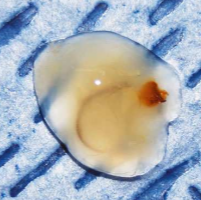

"The Eustachian tube is kept closed by the surface tension caused by contact between air and mucus. A particular agent, identified as a combination of different phospholipids, decreases the surface tension inthe Eustachian tube of dogs, thus reducing the pressure needed to open the tube. When the tube is closed, the pressure in the middle ear is reported to become negative in relation to the pressure in the tube, which is equivalent to atmospheric pressure. This negative pressure, caused by lack of aeration, draws out the sterile transudate from the glandular tissues in the middle ear to the surface of the mucous membrane. The negative pressure remains and the process of accumulation of mucus carries on as long as the tympanic membrane is intact and the Eustachian tube is closed. Failure to open the Eustachian tube and thereby release the secretory products is believed to be the cause of secretory otitis media. An obstruction of the osseous part of the Eustachian tube is reported to be the most common cause. In PSOM, the overfilling of the middle ear with mucus and the subsequent bulging of the tympanic membrane, and the pain and neurological signs that are common, indicate that the pressure within the middle ear is high rather than low, at least in the final part of the disease process." Photo above shows mucus plugs removed from a cavalier. Courtesy, Downs Veterinary Practice, Bristol, UK.